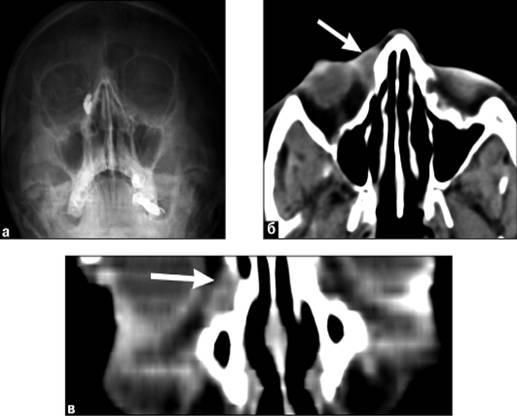

Рентгенография, КТ, МРТ: в верхненаружном отделе

глазницы визуализируется увеличенный слезный мешок с жидким содержимым,

утолщенными и неровными стенками (рис. 16).

Рис. 16. Дакриоцистит: а) дакриоцистограмма; б,

в) компьютерные томограммы